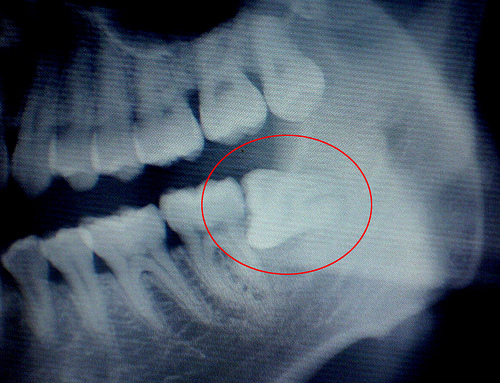

由于智齿萌发的空间比较窄小,智齿很难正常生长,所以会产生疼痛,具体的情况有三种:

第二种,智齿横向生长,别的牙齿都一柱擎天向上长,偏偏智齿会长得横行霸道,一旦碰触到旁边的牙齿,自然会出 现牙疼的情形。智齿疼怎么办?如果智齿长成这样,务必趁早拔掉;

第三种,智齿“蜗居”在牙肉里,有时候你根本就看不到智齿,但依旧会觉得牙疼难当,基本就是这种原因所致。